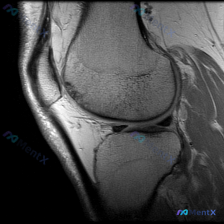

刚看到一份膝关节MRI单矢状位切面的读片需求,核心问题是观察半月板异常,我整理了完整的分析思路分享给大家。 一、病例基本影像信息 这是一张膝关节矢状位MRI影像,根据信号特征判断:不符合典型T1加权像(骨髓信号偏低,关节软骨、积液呈高信号),更符合质子密度加权像(PDWI)或T2加权像,这类序列对半...